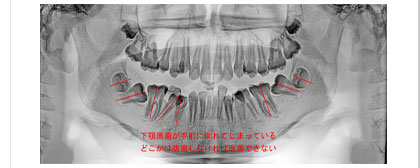

歯の生えてきた位置がおかしい場合。歯の数が多過ぎる場合、少ない場合。

歯並びの凸凹。歯並びの全体の形の不具合。上下の歯のかみ合わせの問題。

実際の歯列不正はさまざまな要因が重なって発生しています。